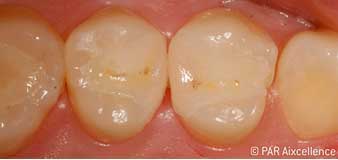

Abb 1: Ausgangsbild der Zähne ohne scheinbare klinische Karies.